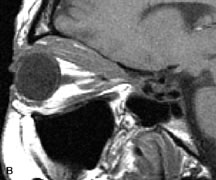

Extraocular muscle enlargement in patients with thyroid-associated orbitopathy is demonstrated equally well with CT and MRI studies. However, the superior tissue contrast on MR images reveals better details of the relationships of the optic nerve to the thickened muscles at the orbital apex (Fig. 16).50 In addition, MRI may be able to differentiate between muscles that are enlarged as a result of edema and active inflammation and those enlarged because of fibrosis by their T2 relaxation times.21 Quantitative MRI was not found to be accurate in predicting the success of low-dose orbital irradiation.51 However, a muscular index relating the diameters of the rectus muscles to the bony orbital dimensions was useful in predicting optic nerve compression.52

Fig. 16. A-C, T1-weighted MR scans obtained with a high-resolution surface coil demonstrate fusiform enlargement of the extraocular muscles. The medial, lateral, and inferior rectus muscles are especially involved. Note the relative sparing of the tendinous insertions, a finding characteristic of this disease process, as well as fatty infiltration of the lateral and inferior rectus muscles. There is marked proptosis, best visualized on the sagittal image (A), and mild crowding of the optic nerve at the orbital apex.